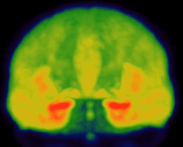

Here is a picture of many research brain PET scans from our group: